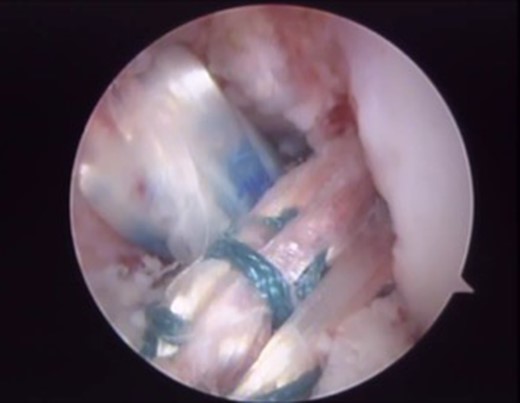

The patient underwent arthroscopic ACL reconstruction using ipsilateral flexor tendons as graft, PCL reconstruction using contralateral flexor tendons as graft and partial meniscectomy (Figs 3–5).

Final arthroscopic surgery image of the ACL and PCL reconstruction with the grafts tense and well positioned.